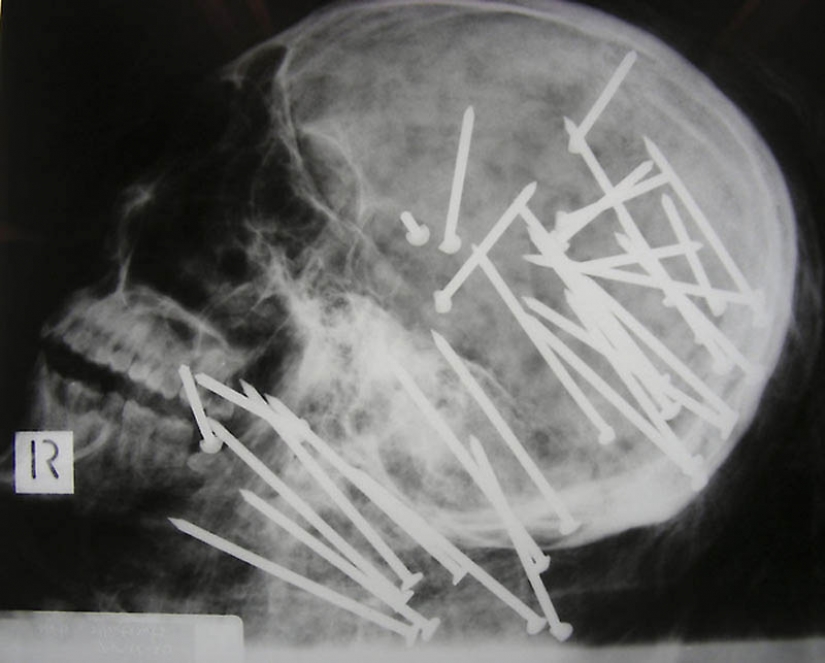

1. El cráneo de un hombre Chino que recibió un disparo en la cabeza con un martillo neumático